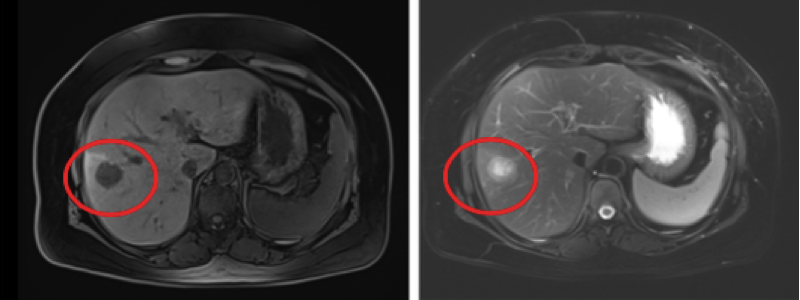

2018年11月5日,复查肝脏增强MRI(图3,4):肝脏多发结节灶,长T2长T1信号,DWI呈高信号,转移瘤考虑,其中右肝Ⅷ段包膜下及Ⅶ段腔静脉旁各见一T2高信号灶,大小分别约27 mm × 24 mm,11.5 mm × 9.8 mm;脂肪肝。

2018年11月7日,行超声引导下肝肿物切割式穿刺活检术,病理结果示:(右肝穿刺)浸润性癌,结合病史及免疫组化,考虑乳腺来源;免疫组化:ER(-)、PR(-)、HER-2(3+)、EGFR(少量+)、Ki-67(40%+),E-Cadherin(+)、P120(+)、Hepatocyte(-)、Arginase-1(-)、CK19(+)、CK20(-)。

图3,4 2018年11月5日 第一次进展 肝脏增强MRI